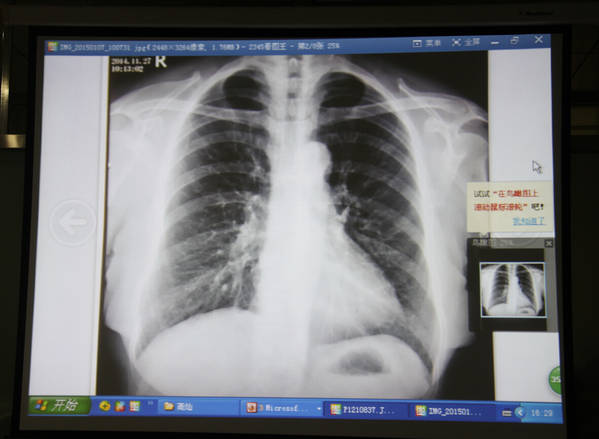

今天下午手外科学术沙龙

讨论手外科结核病的诊治